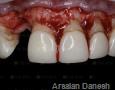

Pictures

Baseline